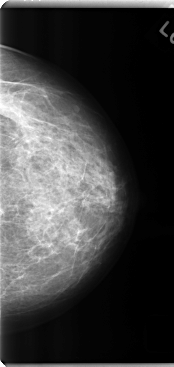

C_0252_1.LEFT_CC

LEFT_CC LINES 4760 PIXELS_PER_LINE 2256 BITS_PER_PIXEL 12 RESOLUTION 50 NON_OVERLAY